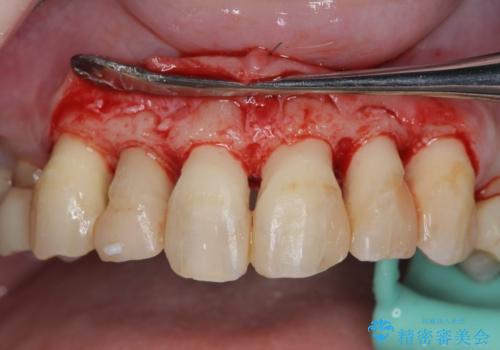

- 放置した虫歯の歯がボロボロになってしまい治療を希望され来院されました。

残根状態の歯、神経まで虫歯が達し失活した歯、歯肉縁下まで及んだ虫歯が多数認められます。

まず虫歯を拡大鏡、マイクロスコープ下で丁寧に取り除き歯肉縁下の虫歯を歯周外科により解決したのち、ジルコニアクラウン製作を行っていきます。